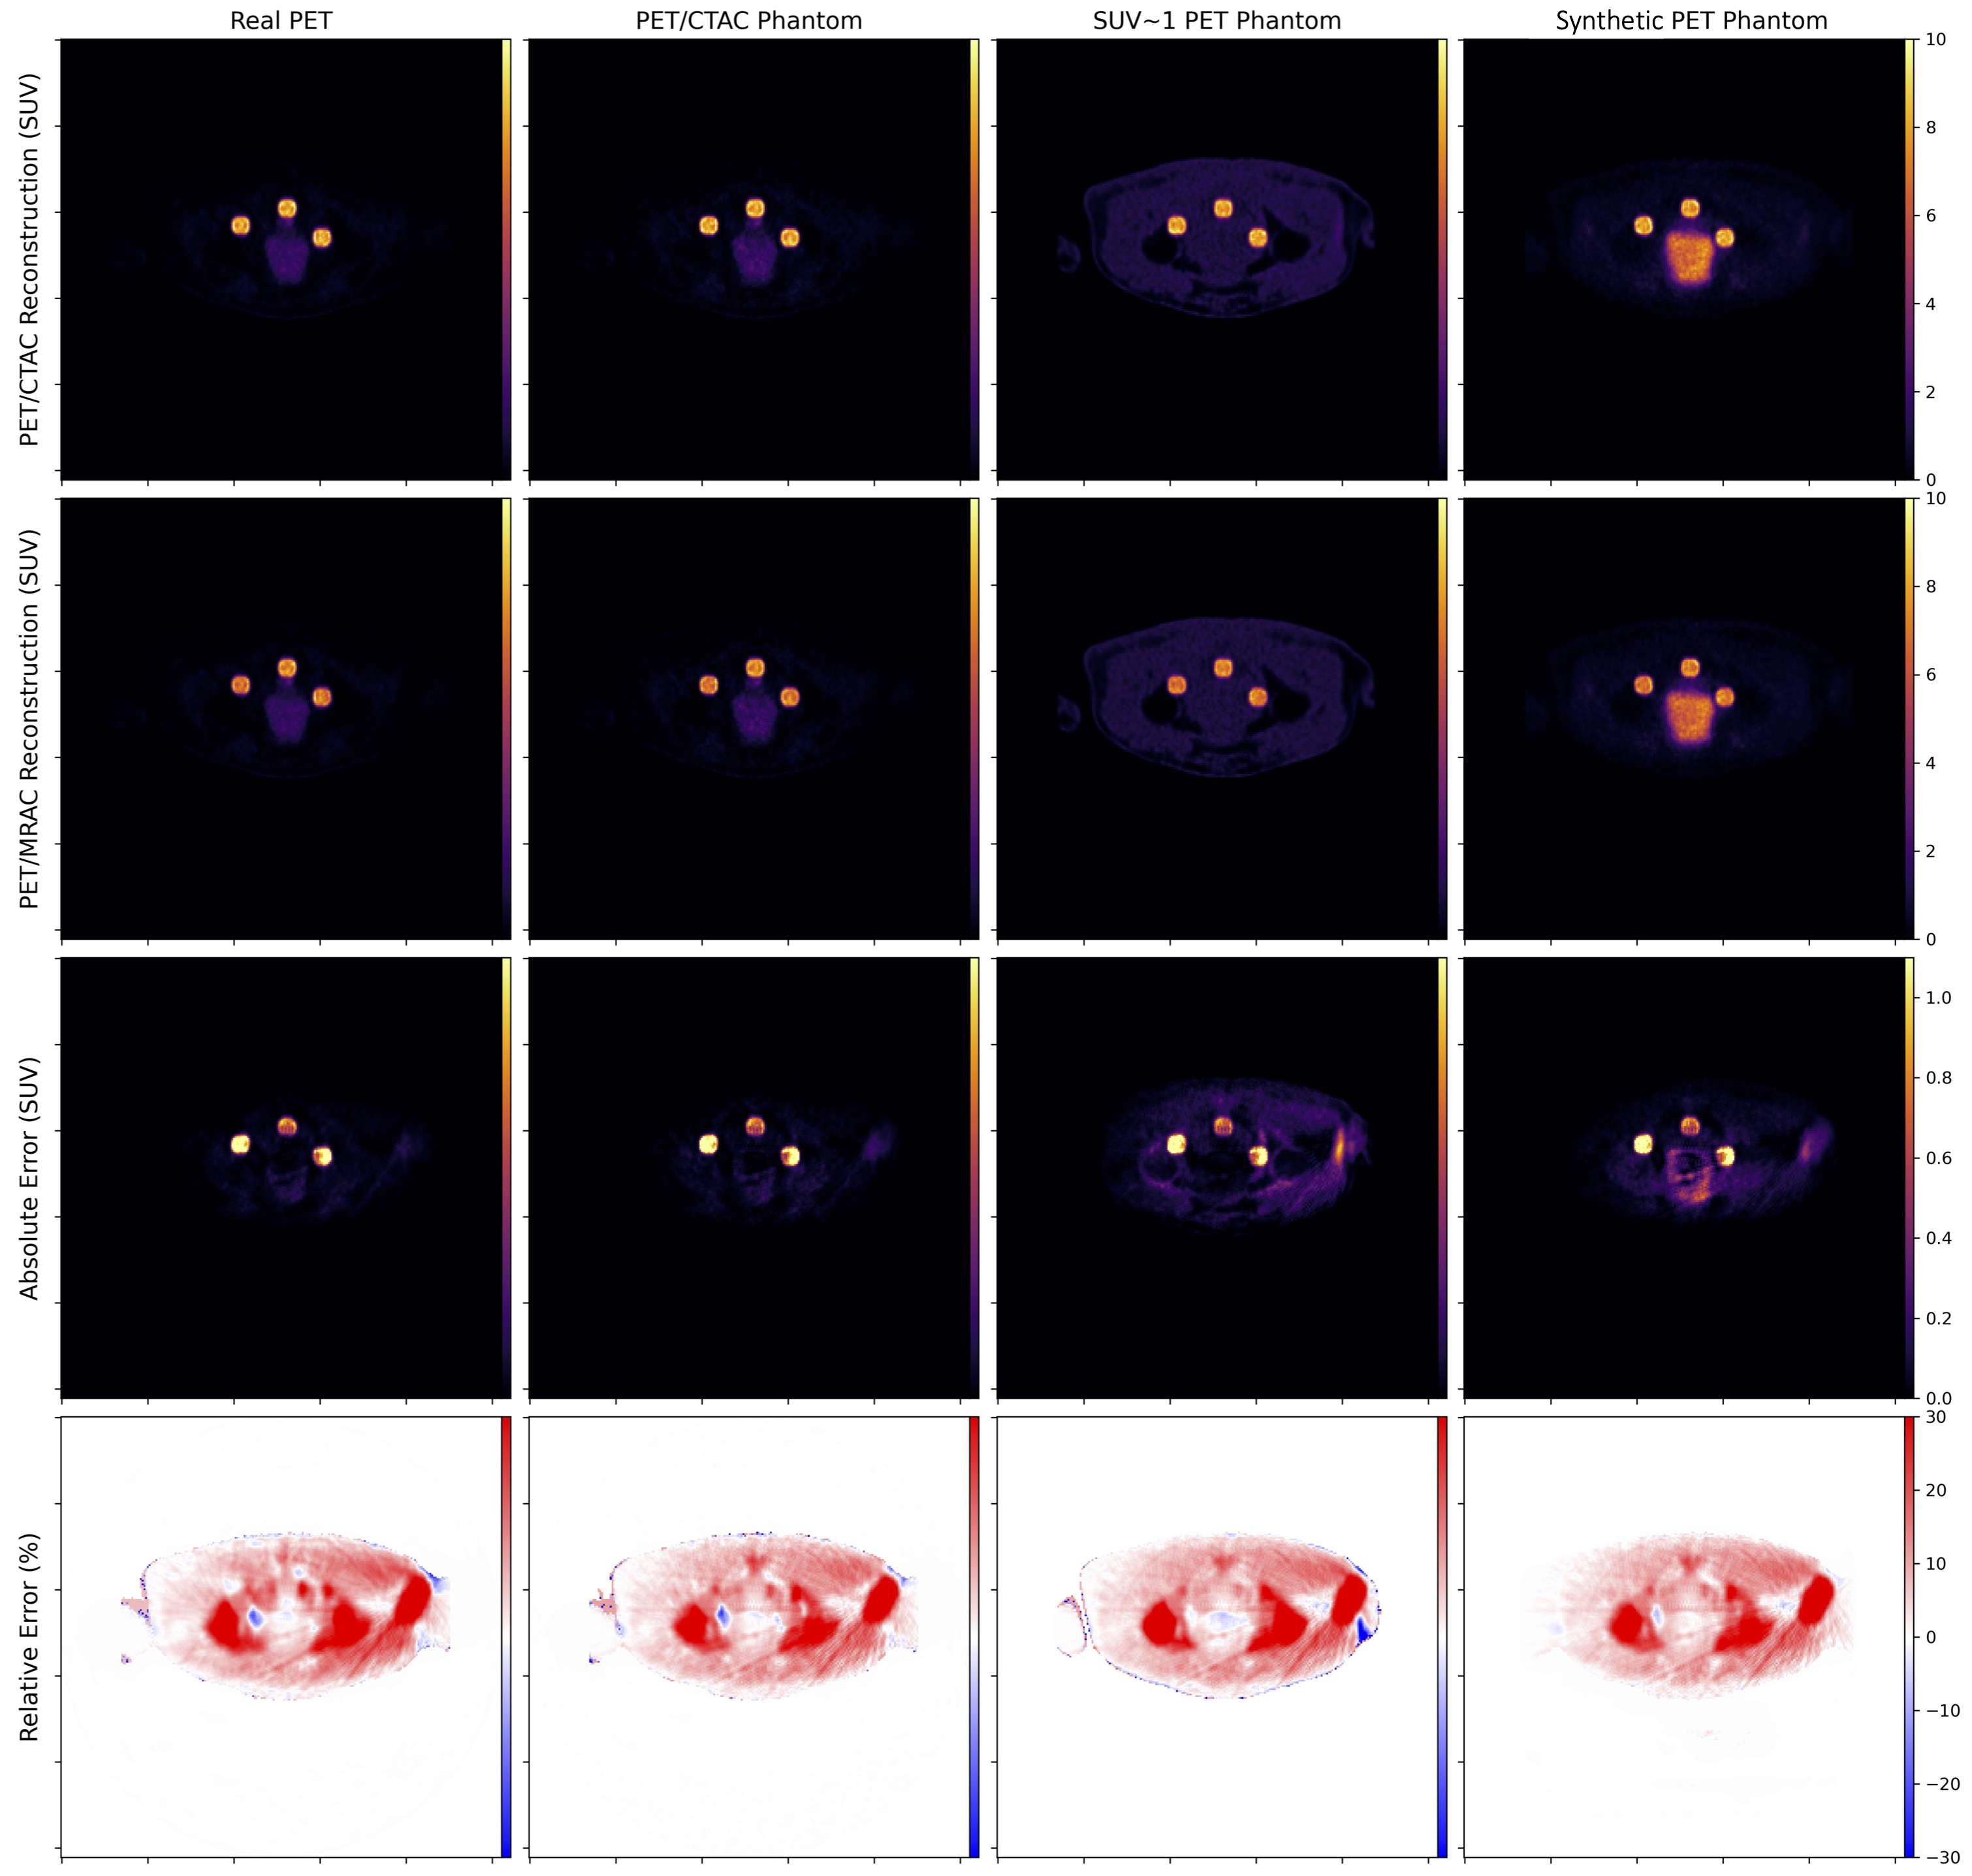

We exploit this mechanism to generate synthetic PET sinogram data from domain-translated synthetic PET imagery. However, as Duetto currently does not incorporate scatter simulation, we perform reconstructions with scatter estimation and correction turned off. As this introduces an additional discrepancy between real PET and synthetic PET reconstructions, in both cases we start by forward projecting a 3D “source” volume to yield a simulated ToF-sinogram that is subsequently inserted with synthetic lesions (Fig. 4).

For each patient exam we select 5 different VOIs: lesion voxels corresponding to the four annotated regions (acetabulum, sacrum, rectum, and lymph), and “background”, representing all non-zero voxels outside of the synthetic lesions. Quantification error is computed for each VOI by comparing mean-, max-, and peak-SUV between CTAC-based and MRAC-based reconstructions. Subsequently we compare the quantification error predicted by each PET data source to that predicted by the aforementioned reconstructed PET/CTAC live phantom. The absolute error is quantified for the background pixels, but the relative error is not since many voxels are devoid of any activity, positively skewing (overestimating) the mean relative error computation. In lieu of individual regions within the pelvis, the relative error in background voxels is better evaluated qualitatively by comparing slices in the transverse plane (Fig. 5).

3.4 Results on Pelvic 18F-FDG PET/MR/CT Datasets

Numerical results presented in Tables 3-4 indicate that domain-translated MR-based synthetic PET (sPET) can achieve low absolute and relative deviation in quantification error compared to the quantification error predicted by the live PET/CTAC phantom source for synthetically-inserted pelvic lesions. Table 3 shows that sPET-based evaluation to compare CTAC and MRAC-based reconstruction achieves SUV errors that were very similar to the measured PET-based evaluation across inserted lesions and in the background. The percent quantification errors in Table 4 shows that sPET-based evaluation was more similar to measured PET-based evaluation than uniform SUV1-based evaluation, outperforming for mean-SUV evaluations across lesion types. This suggests the applicability of synthetic sPET as a suitable replacement for real measured PET in PET-SUV quantification tasks. In the supplementary material (Figure 6 and 7), we provide Bland-Altman plots that compare the CTAC-vs-MRAC error computed by the various types of phantoms and the Live Phantom. Each column represents a different synthetic PET phantom. Each row represents a different error metric (absolute error or relative error in mean-SUV, peak-SUV, or max-SUV). This analysis shows no significant differences between sPET and measured PET using the aforementioned figures of merit.